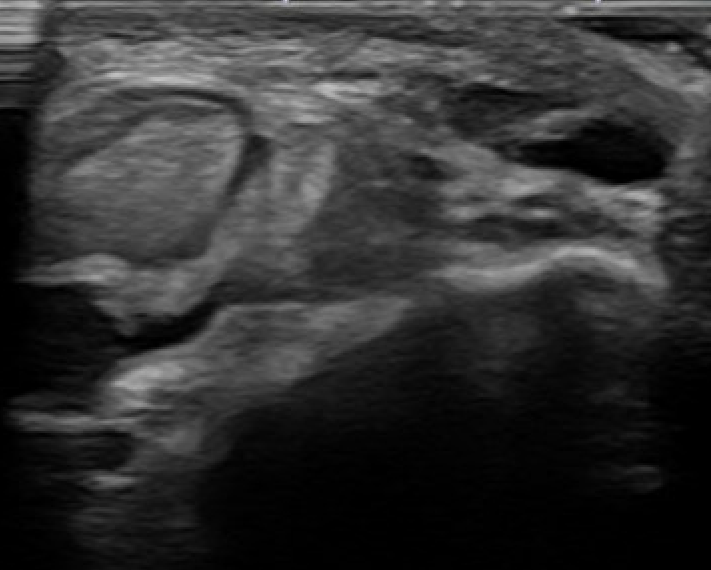

Dynamic Ultrasound

Demonstrates dynamic subluxation

MRI

Anterior subluxation of peroneal tendons

Anterior subluxation of peroneal tendons

Anterior subluxation of the peroneal tendons with dorsiflexion